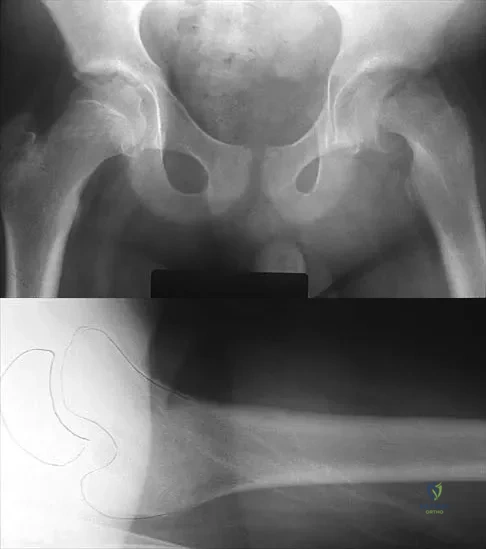

Figures 10a through 10c show the plain radiograph and MRI scans of a 41-year-old man who has right hip pain. What is the most likely diagnosis?

Explanation